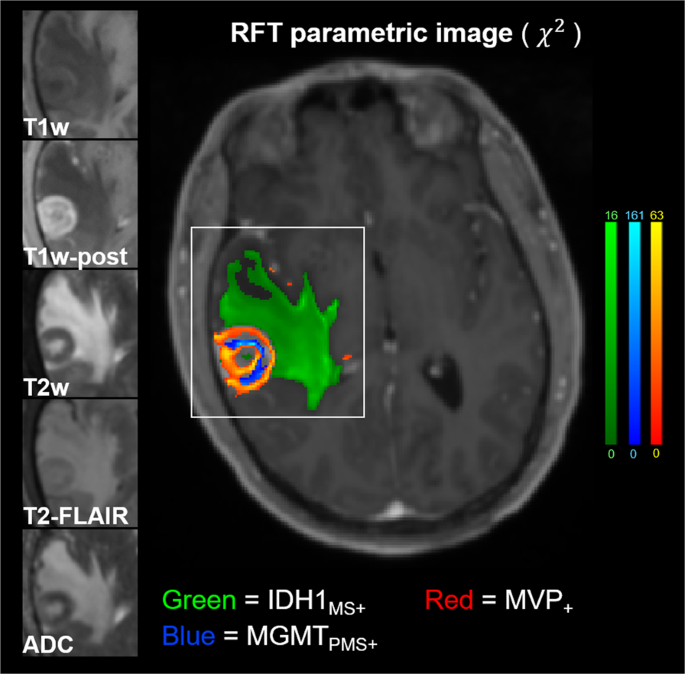

Figure 6 shows an example GBM subject had significant results for all 3 outcome variables that nearly covered the entire TME (Subject 8). The 5 predictor contrasts are shown along the left side of the image zoomed-in on the tumor bed and TME. The colormaps are windowed from 0 to the maximum χ2RFT statistic (right side colorbars). Potential significant findings for MVP+ outside the T2-FLAIR abnormality (3 red speckles frontal and medial to the tumor) may hold important information related to microscopic disease spread.